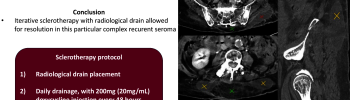

Recurrent Postoperative Seroma and Fistula After Lumbar Spine Instrumentation: A Case Report and Doxycycline Sclerotherapy Protocol